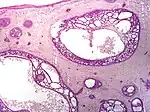

Other more specific subtypes of basal-cell carcinoma include:[19][2]

Type | Histopathology | Other characteristics | Image |

---|---|---|---|

Cystic basal-cell carcinoma | Morphologically characterized by dome-shaped, blue-gray cystic nodules.[2] | ![]() | |

Morpheaform basal-cell carcinoma (also known as "cicatricial basal-cell carcinoma", and "morphoeic basal-cell carcinoma") | Narrow strands and nests of basaloid cells, surrounded by dense sclerotic stroma.[20] | Aggressive[19]: 748 [2] | ![]() |

Infiltrative basal-cell carcinoma | Deep infiltration.[2] | Aggressive[2] | |

Micronodular basal-cell carcinoma | Small and closely spaced nests. | ![]() | |

Superficial basal-cell carcinoma (also known as "superficial multicentric basal-cell carcinoma") | Occurs most commonly on the trunk and appears as an erythematous patch.[19]: 748 [2] | ![]() | |

Pigmented basal-cell carcinoma exhibits increased melanization.[19]: 748 [2]: 647 | About 80% of all basal-cell carcinoma in Chinese are pigmented while this subtype is uncommon in white people. | ||

Rodent ulcer (also known as a "Jacob's ulcer") | Nodular, with central necrosis.[19]: 748 [2] | Generally a large skin lesion with central necrosis.[19]: 748 [2] | |

Fibroepithelioma of Pinkus | Anastomosing epithelial strands in a fenestrated pattern[21] | Most commonly occurs on the lower back.[19]: 748 [2] | ![]() |

Polypoid basal-cell carcinoma | Exophytic nodules (polyp-like structures) | Generally on head and neck.[2] | |

Pore-like basal-cell carcinoma | Resembles an enlarged pore or stellate pit.[2] | ||

Aberrant basal-cell carcinoma | Absence of any apparent carcinogenic factor, and occurring in odd sites such as the scrotum, vulva, perineum, nipple, and axilla.[2] |